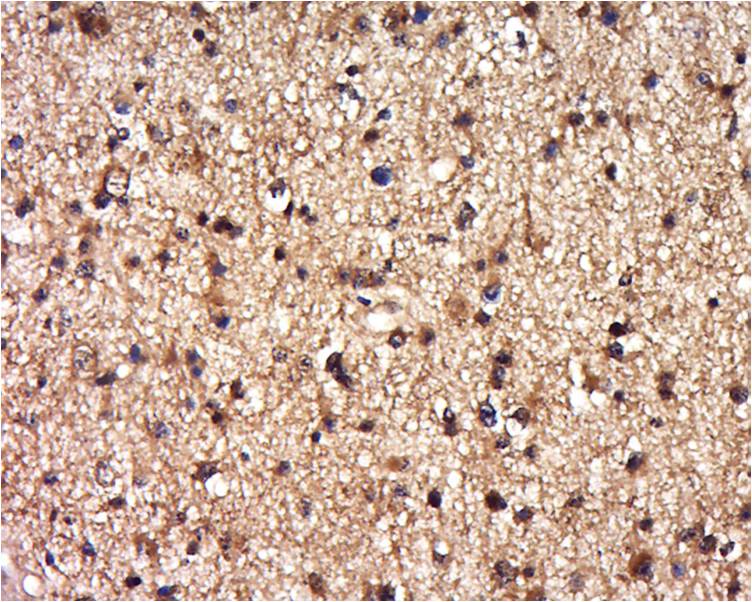

Tissue/cell: human brain glioma; 4% Paraformaldehyde-fixed and paraffin-embedded; Antigen retrieval: citrate buffer ( 0.01M, pH 6.0 ), Boiling bathing for 15min; Block endogenous peroxidase by 3% Hydrogen peroxide for 30min; Blocking buffer (normal goat serum,C-0005) at 37℃ for 20 min; Incubation: Anti-BRCC3 Polyclonal Antibody, Unconjugated(bs-14278R) 1:500, overnight at 4°C, followed by conjugation to the secondary antibody(SP-0023) and DAB(C-0010) staining